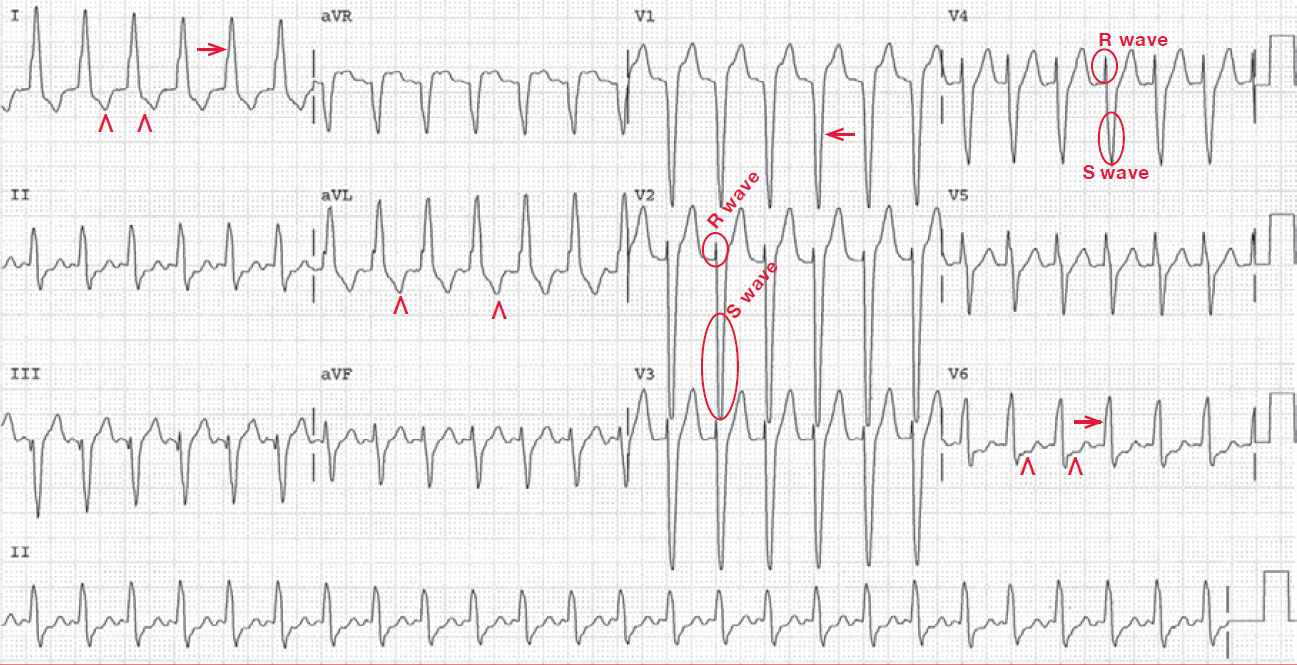

The following ECG recorded her heart rate has slowed shows sinus rhythm with LBBB, so this confirms that the diagnosis of the previous ECG was indeed AVNRT with aberrancy (LBBB).